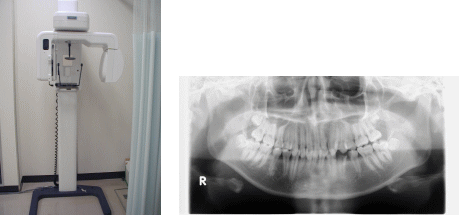

パノラマ撮影

歯や顎の骨を1枚の写真の中に横一列に撮影することができる画像検査です。パントモグラフィーとも言います。

機械が顔の周りを回りながら撮影します。当院では主に、歯の周りや顎を骨折したときに撮影しています。

パノラマ撮影装置